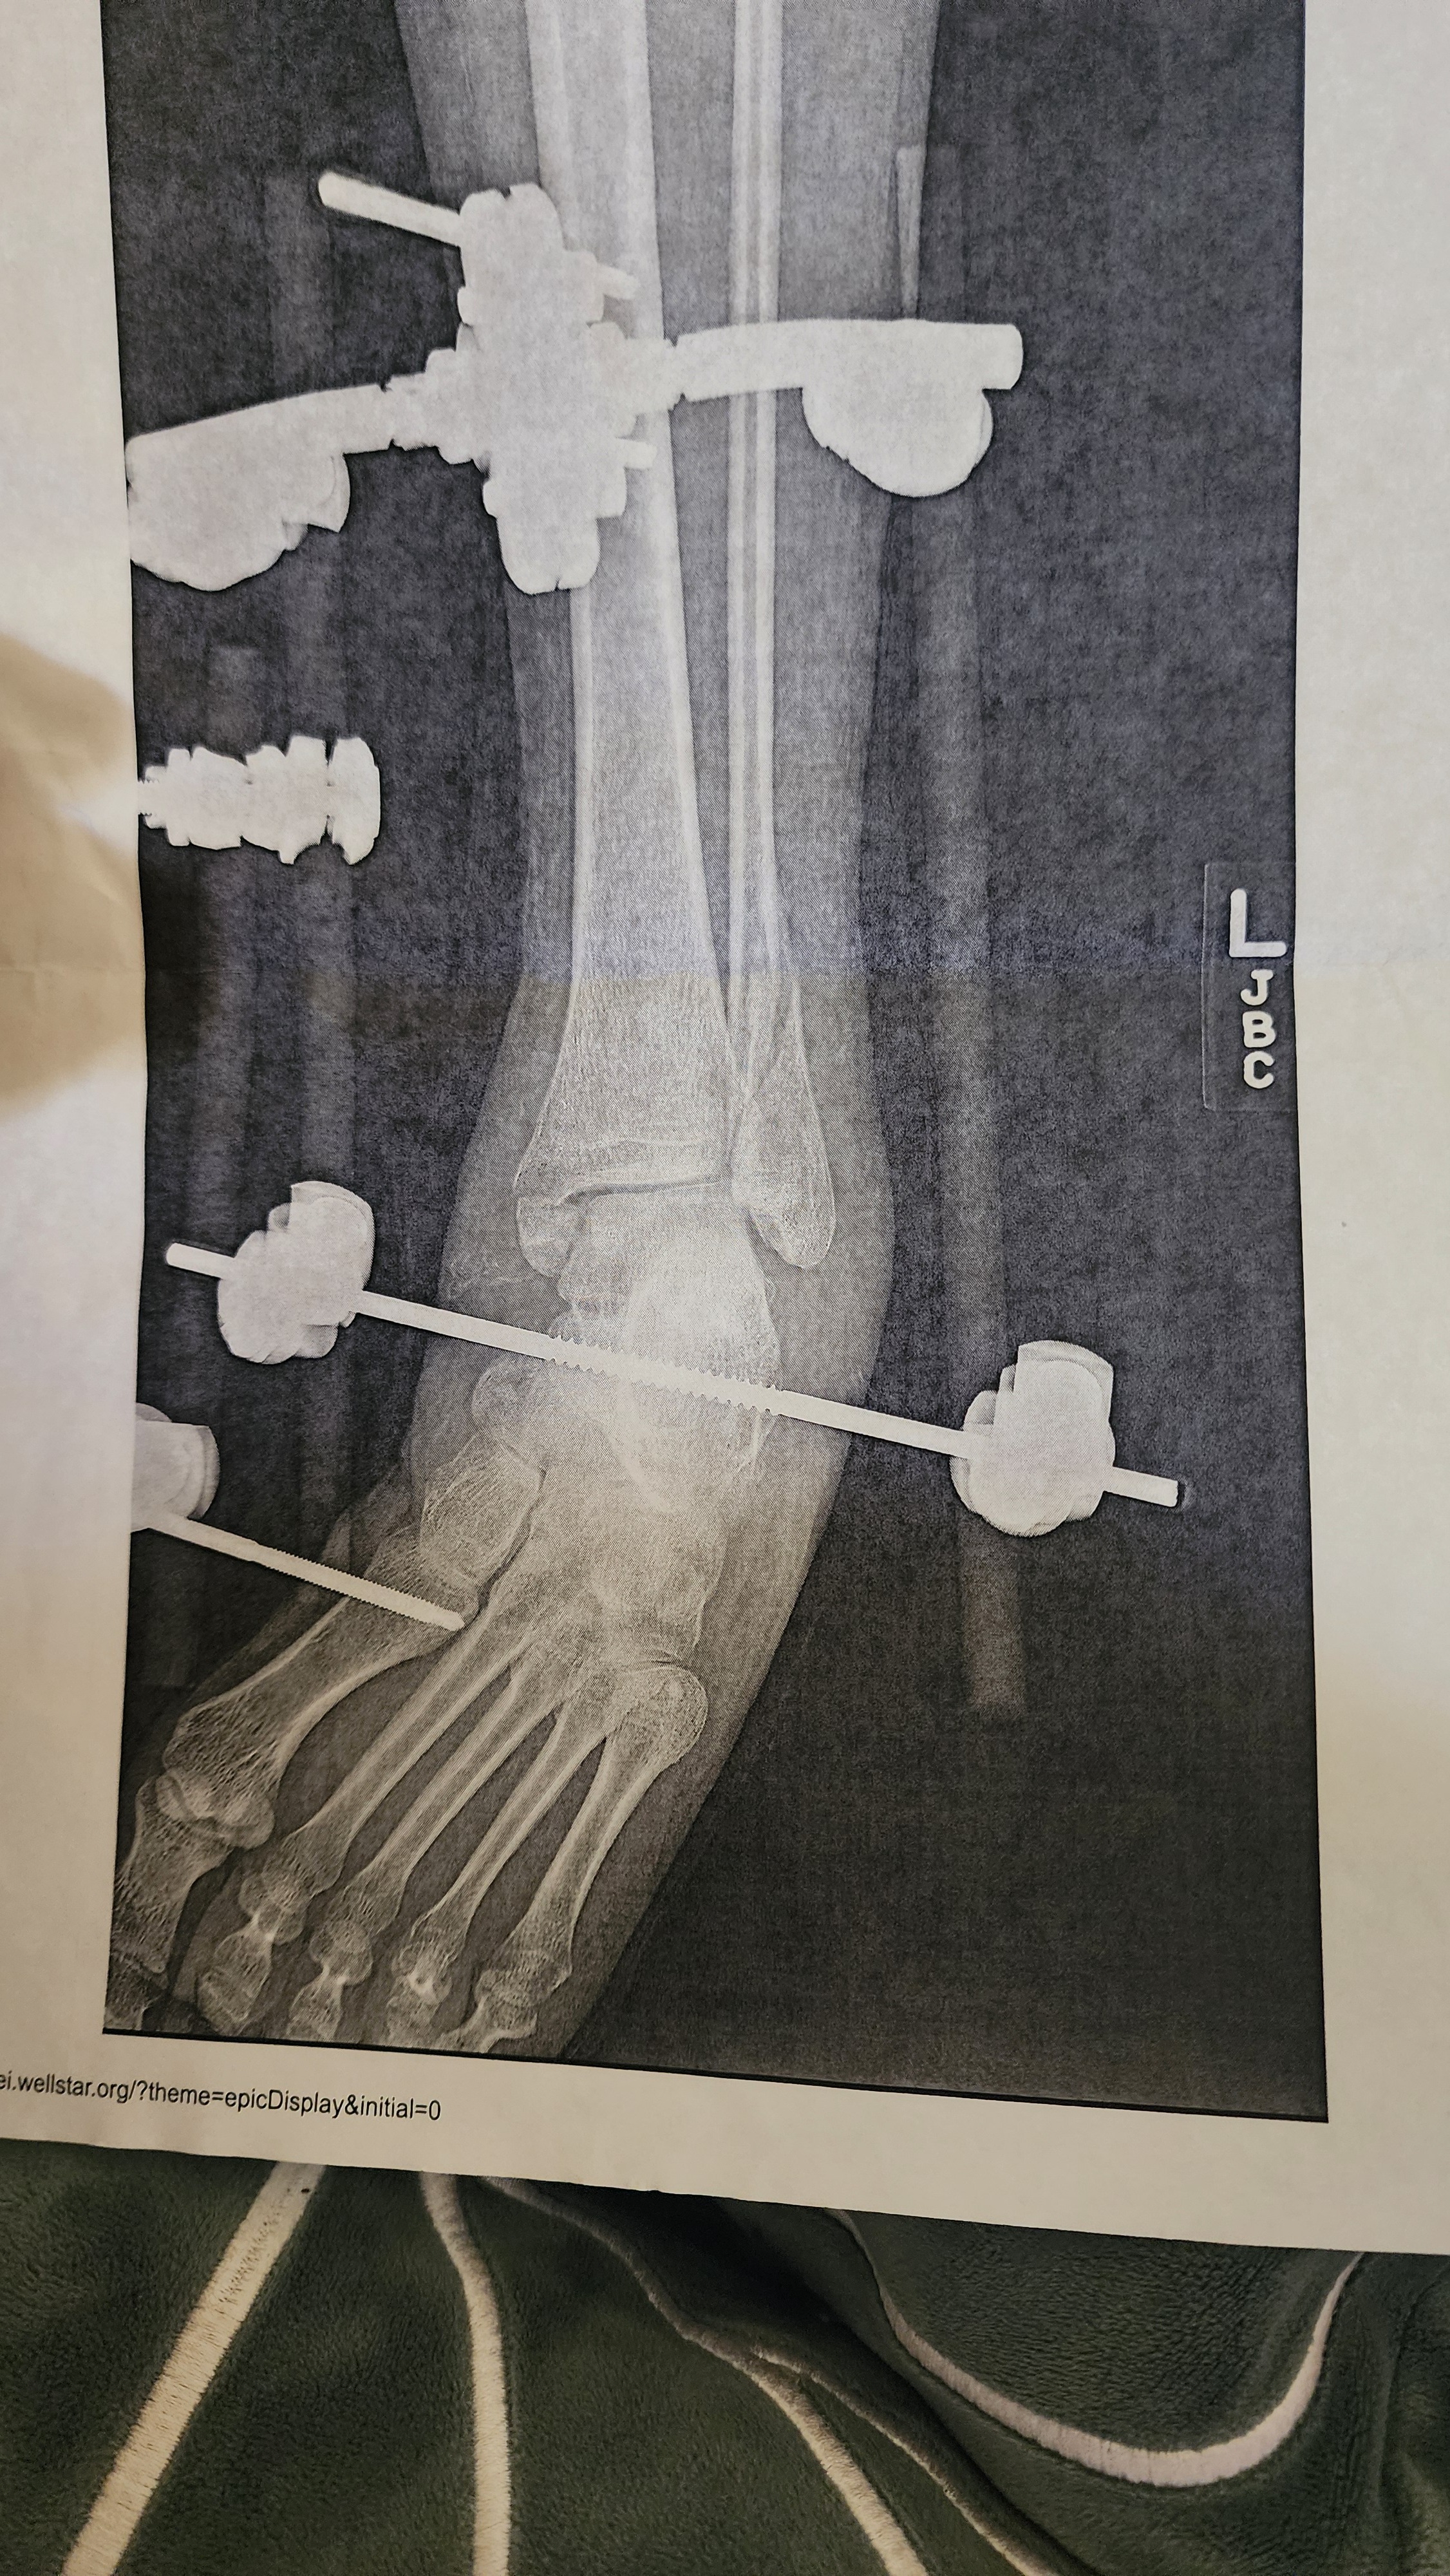

Unfortunately, while I was celebrating a friend's birthday, I fell and broke my ankle in 3 places. It's the first time I've broken a bone. It was a pretty terrible experience, but it got worse later dealing with the pain, discomfort, and having the patience of being confined and not being able to do much for myself. I ended up having a few complications and found out I need to have two surgeries.